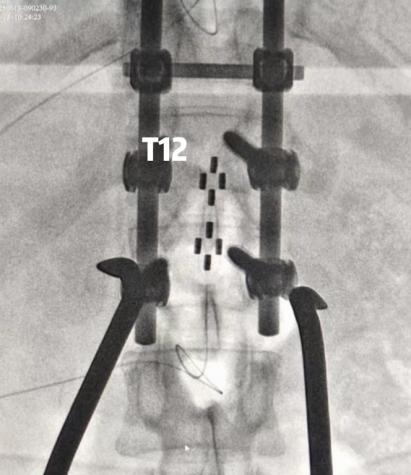

脊髓电刺激选用2-4-2触点排布的片状电极(外科电极),分别植入T8-T9以及T12-L1节段,术中结合影像并通过开启刺激诱发出特定部位的肌电,来确定上方电极位置的准确性。

图片图片

术中影像